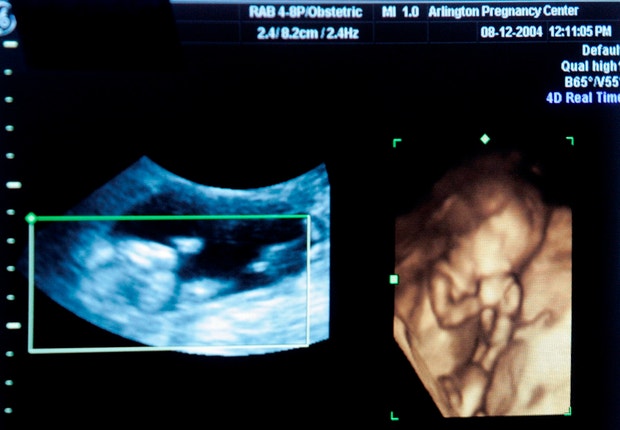

Caso do bebé sem rosto. Inquérito da ARS revela indícios de utilização irregular das requisições dos exames ecográficos